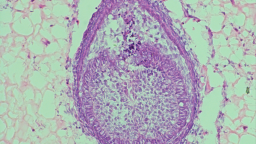

Dr. Xuechen Zhang Scientists are racing to grow human teeth in the lab